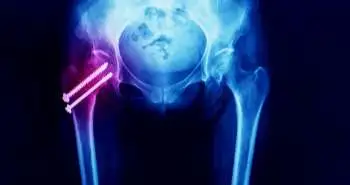

Performing bone densitometry without consideration to side of greater weakness may lead to underestimation of BMD and under treatment of femoral neck fractures in the high-fall-risk patients.

Evaluation of bone mineral density (BMD) is an essential factor for estimating fractures of the femoral neck, as per the analysis published in the Journal, PM & R. The subjects with the long-term residual lower extremity (LE) weakness after polio exhibited reduced BMD, linked with the weakness of muscles.

Therefore, in the little sample, using strong-limb T scores ended in fewer people described as having osteoporosis or low bone density than when weak-limb T scores were used. Depreciating BMD loss may involve inadequate treatment and enhanced risk of mortality, morbidity, and costs linked with osteoporosis of femoral neck in this high-fall-risk class. This implies a significant association of BMD and femoral neck fractures.